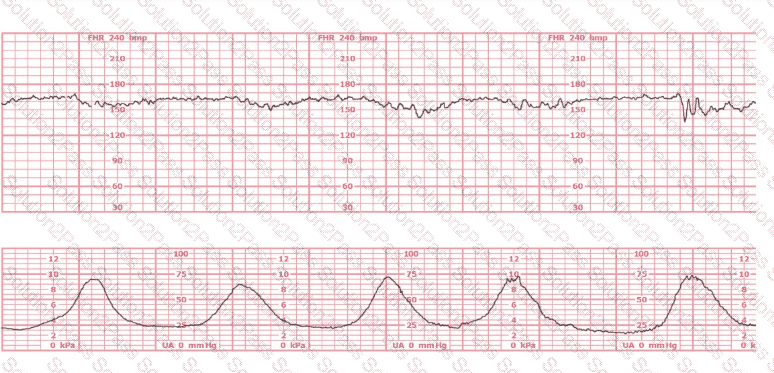

This is a fetal heart rate tracing of a multiparous woman whose cervix is 7 cm dilated on admission. The most likely cause for this pattern is:

This is a tracing of a multiparous woman in the second stage of labor. The vertex is at +3 station. This pattern has continued for the last 20 minutes. She has been pushing for 2½ hours, and oxytocin is infusing at 12 milliunits/minute. Management should include